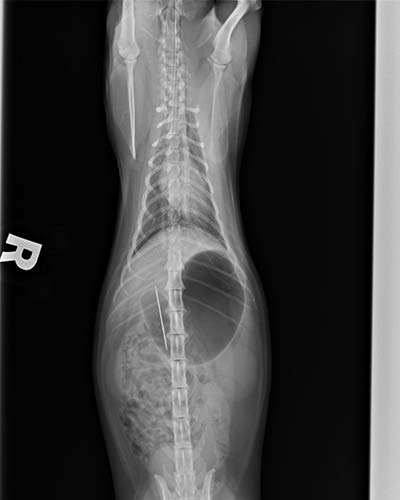

仰照也可以看到針的位置

胃中可見邊緣尖銳的骨頭